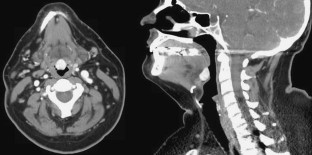

Lingual thyroid is a rare condition in which ectopic thyroid tissue is present in the base of tongue. We present a case of a 46-year-old patient with a symptomatic lingual thyroid that was successfully removed with minimal morbidity using transoral robotic surgery. The traditional treatment algorithm for lingual thyroid is reviewed. The advantages of using transoral robotic surgery to remove lingual thyroid tissue are described along with the reasons why the addition of this technique should shift treatment of lingual thyroid towards more frequent use of surgical ablation. This report is, to our knowledge, the first describing the use of transoral robotic surgery for treating lingual thyroid.

Fig. 1